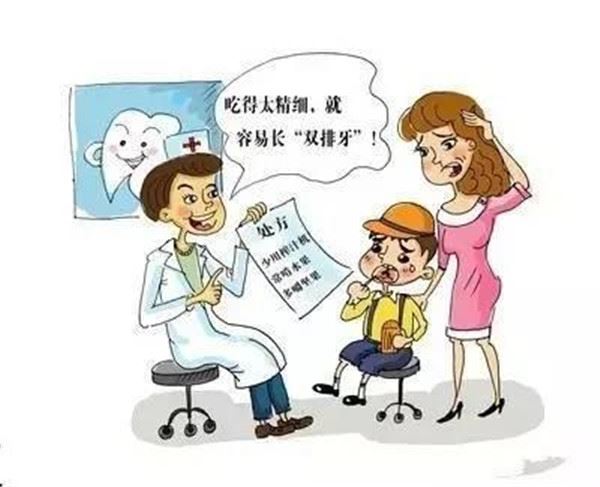

近年來,「雙排牙」寶寶增多,多是因為現在的寶寶營養過剩,另外進食也過於精細、鬆軟,無法使牙齒得到足夠的鍛煉。

3.飲食過於精細

上述八歲男孩的媽媽說道:兒子從小就偏食、好甜飲,把旺仔牛奶等甜乳製品當水喝,一天三、四瓶。在檢查中醫生髮現,乳牙牙根已經暴露於牙齦粘膜之外,容易導致附近口腔粘膜創傷性潰瘍。當務之急,需要實施局部麻醉拔出乳牙。